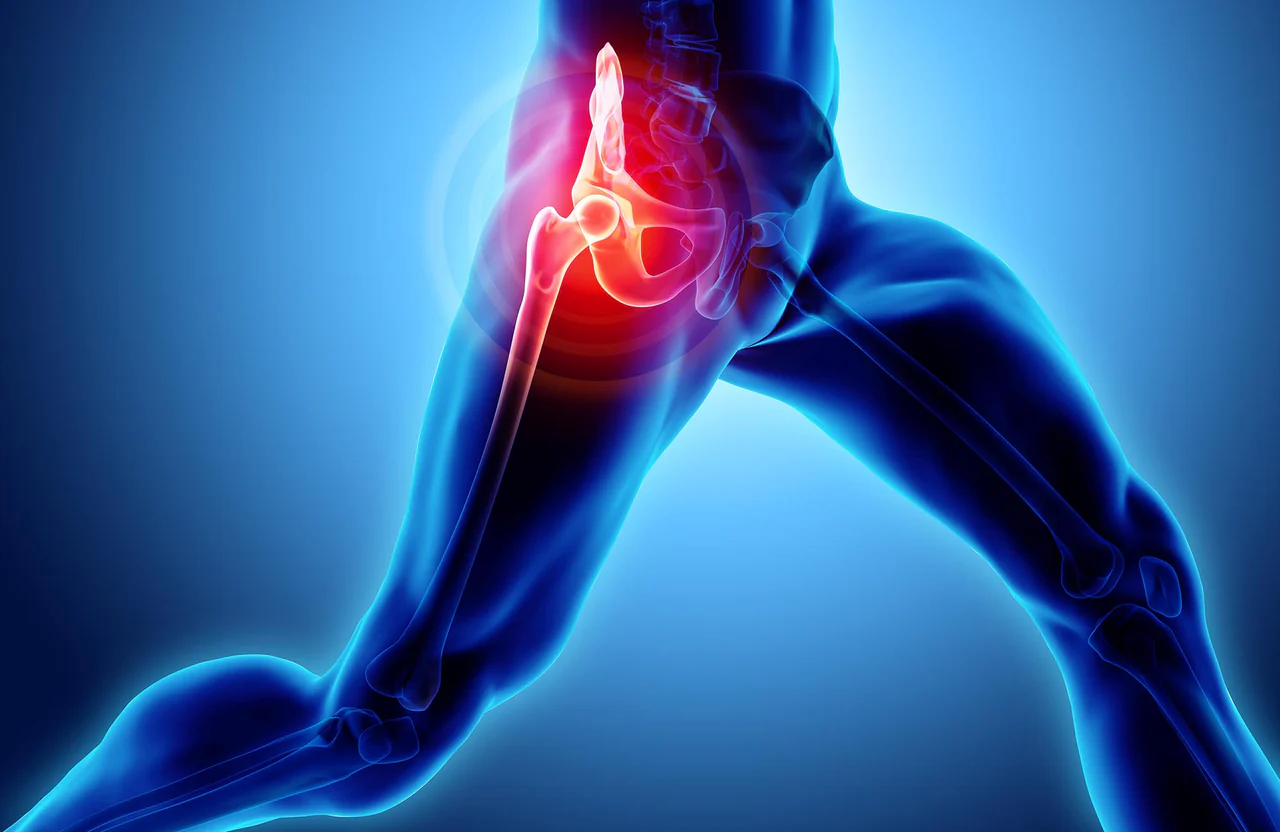

その股関節の痛み、放置しないで!

「歩き始めに股関節がズキッとする」「長く座ったあと立ち上がると痛む」

最初は軽い違和感でも、放置すると日常の動作に支障が出てしまうことがあります。

股関節は“体を支える大黒柱”。早めのケアが元気な動きを守るカギです!

股関節痛の主な原因

長時間の座りっぱなしや立ちっぱなし

骨盤や背骨のゆがみからくる負担

運動不足による筋力低下

加齢や出産後に起こる軟骨や靭帯の変化

過度なスポーツや無理な姿勢

股関節は上半身と下半身をつなぐ関節なので、少しのゆがみや負担が痛みにつながりやすいのです。